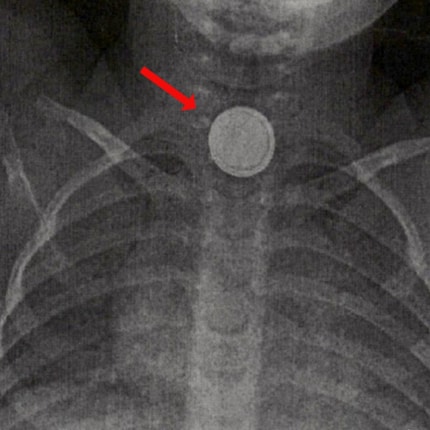

Batteries can be life-threatening if they get stuck in the oesophagus. This is because contact with moist mucous membranes and tissue fluids results in a current flow and thus severe burns. Just a few minutes after ingestion, there’s a risk of devastating consequences with permanent damage or even death.